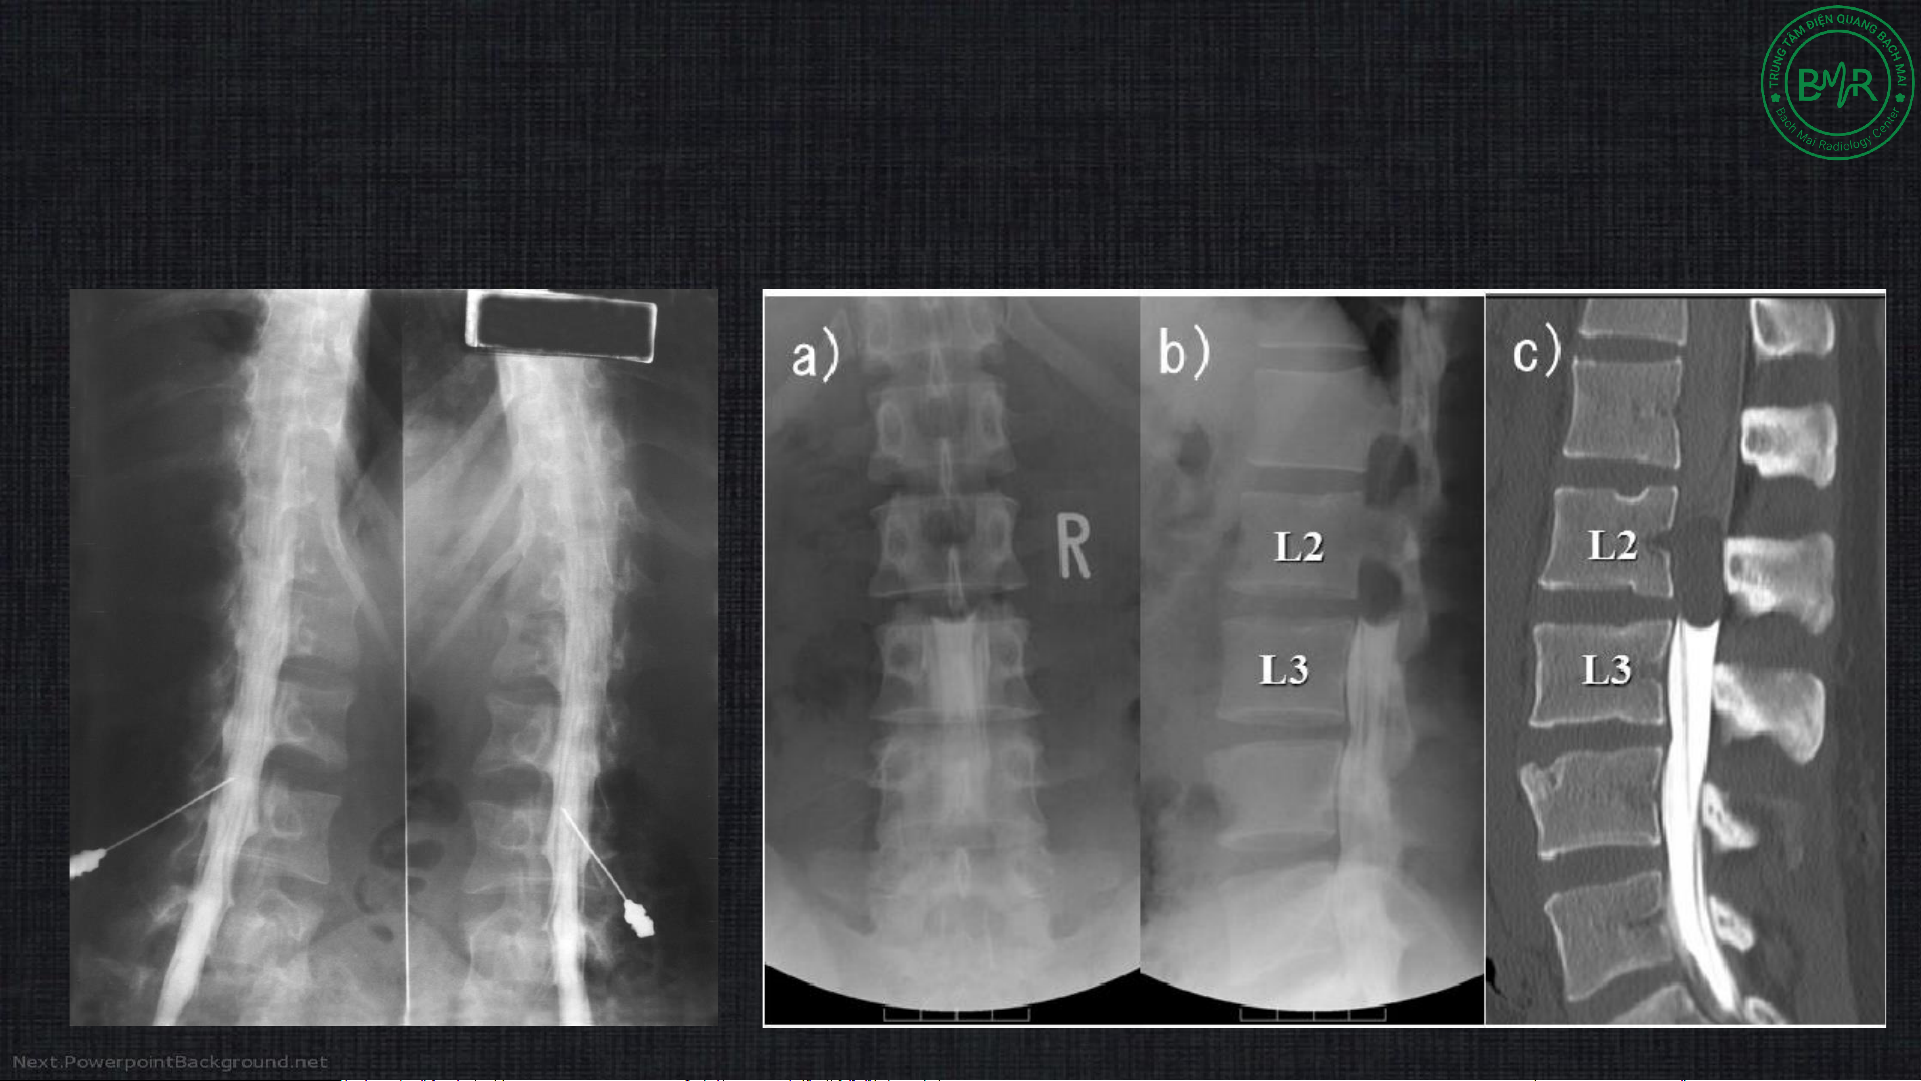

2c. Chụp tủy sống (myelography)

• Xâm lấn, kết hợp Xquang/ CLVT đánh giá tủy sống tốt hơn X quang CLVT CLVT X quang